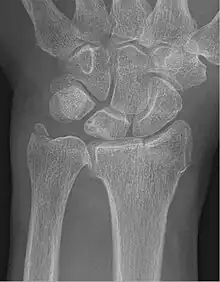

Fracture of the radial styloid process with the fracture line extending into the intraarticular surface

X-ray of a displaced intra-articular distal radius fracture in an external fixator. The articular surface is widely displaced and irregular. This is a Chauffeur's fracture. Frykman class 3.

Chauffeur's fracture, also known as Hutchinson fracture, is a type of intraarticular oblique fracture of the radial styloid process in the forearm.[1] The injury is typically caused by compression of the scaphoid bone of the hand against the styloid process of the distal radius. It can be caused by falling onto an outstretched hand. Treatment is often open reduction and internal fixation, which is surgical realignment of the bone fragments and fixation with pins, screws, or plates.